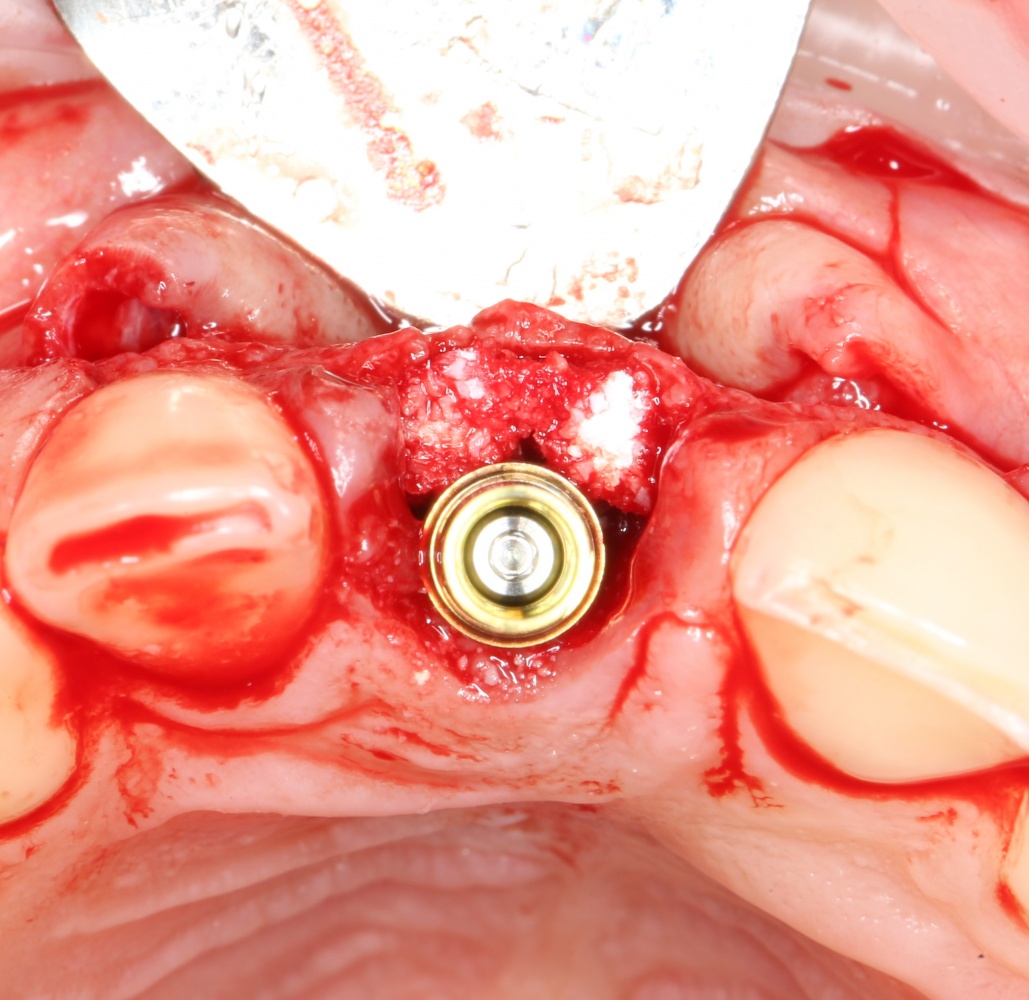

Устанавливается имплантат Astratech (Dentsply Implants):

Для аугментации также используем Bio-Oss Collagen 100 mg, нарезаем его по размеру с помощью скальпеля и позиционируем в лунках щечных корней:

На имплантат ставим формирователь, ушиваем лунку. Напомню, что любой биоматериал должен быть герметично запечатан в ране (фактор успеха III). В противном случае, от него больше вреда, чем пользы: